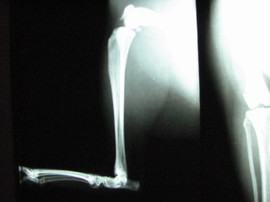

Normal_feline_pelvic_limb

Here is an X-ray of a normal feline rear leg. You can see that straight vertical limb — that’s the tibia, which is the shin bone in humans.  The fibula, which is much smaller and lighter in structure, runs along behind it and isn’t visible in this X-ray.  The tibia and fibula connect to the femur, or thigh bone, at the top of the image.